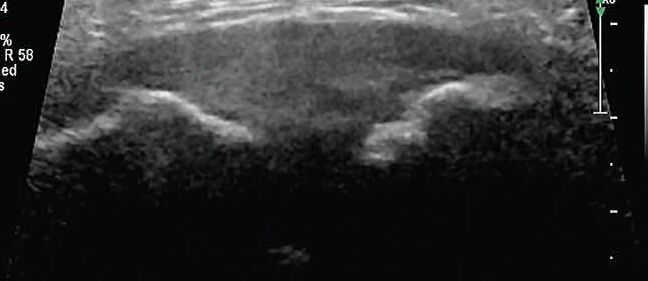

周女士怀孕已经39周了,但作为一个即将迎接新生命的准妈妈来说,她最近却高兴不起来。因为耻骨联合部位走路时痛,上下车、上下楼梯时会更痛,甚至在床上翻身和起床都有困难。于是,在家人的陪伴下,她来到了我院就诊。医生通过对周女士的耻骨联合超声检查发现,其耻骨联合部位明显分离达到了15mm,这就是其疼痛的原因。

耻骨联合分离常用的诊断方法为X射线、CT或MIR检查,但这些检查方法对孕期胎儿均有一定的影响或者价格昂贵,孕妇较难接受。超声作为一种安全、无创、准确的检查方法,可为耻骨联合分离诊断提供较准确的依据,值得在临床推广应用。如孕期或产后出现耻骨联合部位疼痛等相关症状时,可进行超声检查明确诊断,同时咨询产科和产后康复医师给予专业指导和对症治疗。